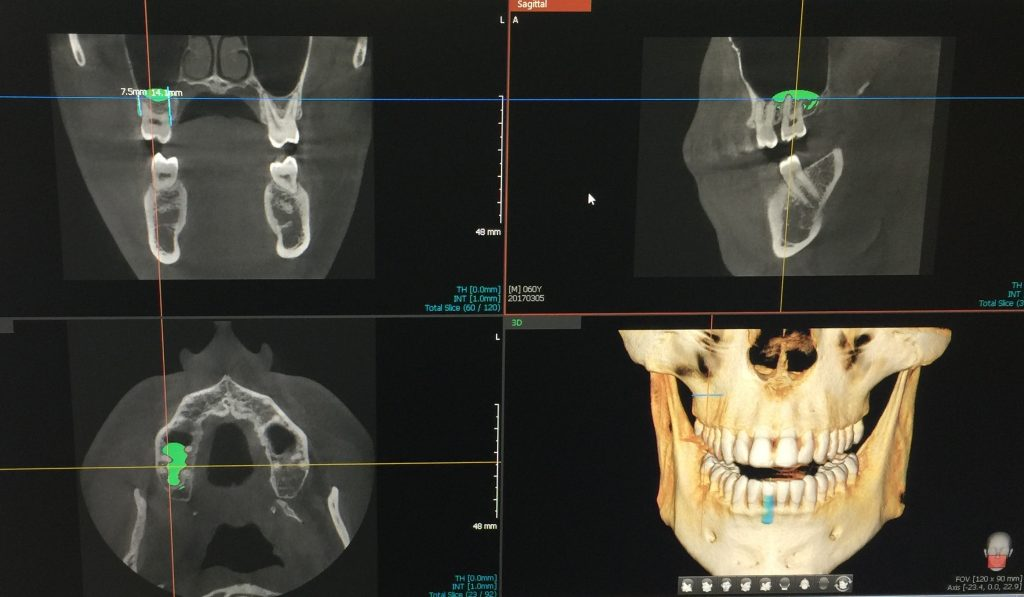

We use the latest Cone Beam Computed Tomography (CBCT) technology right here in Dallas, Richardson, Garland, and Addison to make your dental surgery safer and more accurate.

Our best dentists in Dallas are specially trained to use CBCT, which takes detailed 3D pictures of your teeth, jaw, nerves, and nearby areas. These sharp, high-quality images help us understand exactly what your mouth needs and create a treatment plan just for you.

Unlike regular X-rays, CBCT gives us precise measurements that help during important procedures like dental implants, tooth removal, and jaw treatments, making your care more exact and successful.

- Jaw Surgery: We use precise tools like 3D imaging to plan and perform surgery carefully and effectively for issues like jaw misalignment.